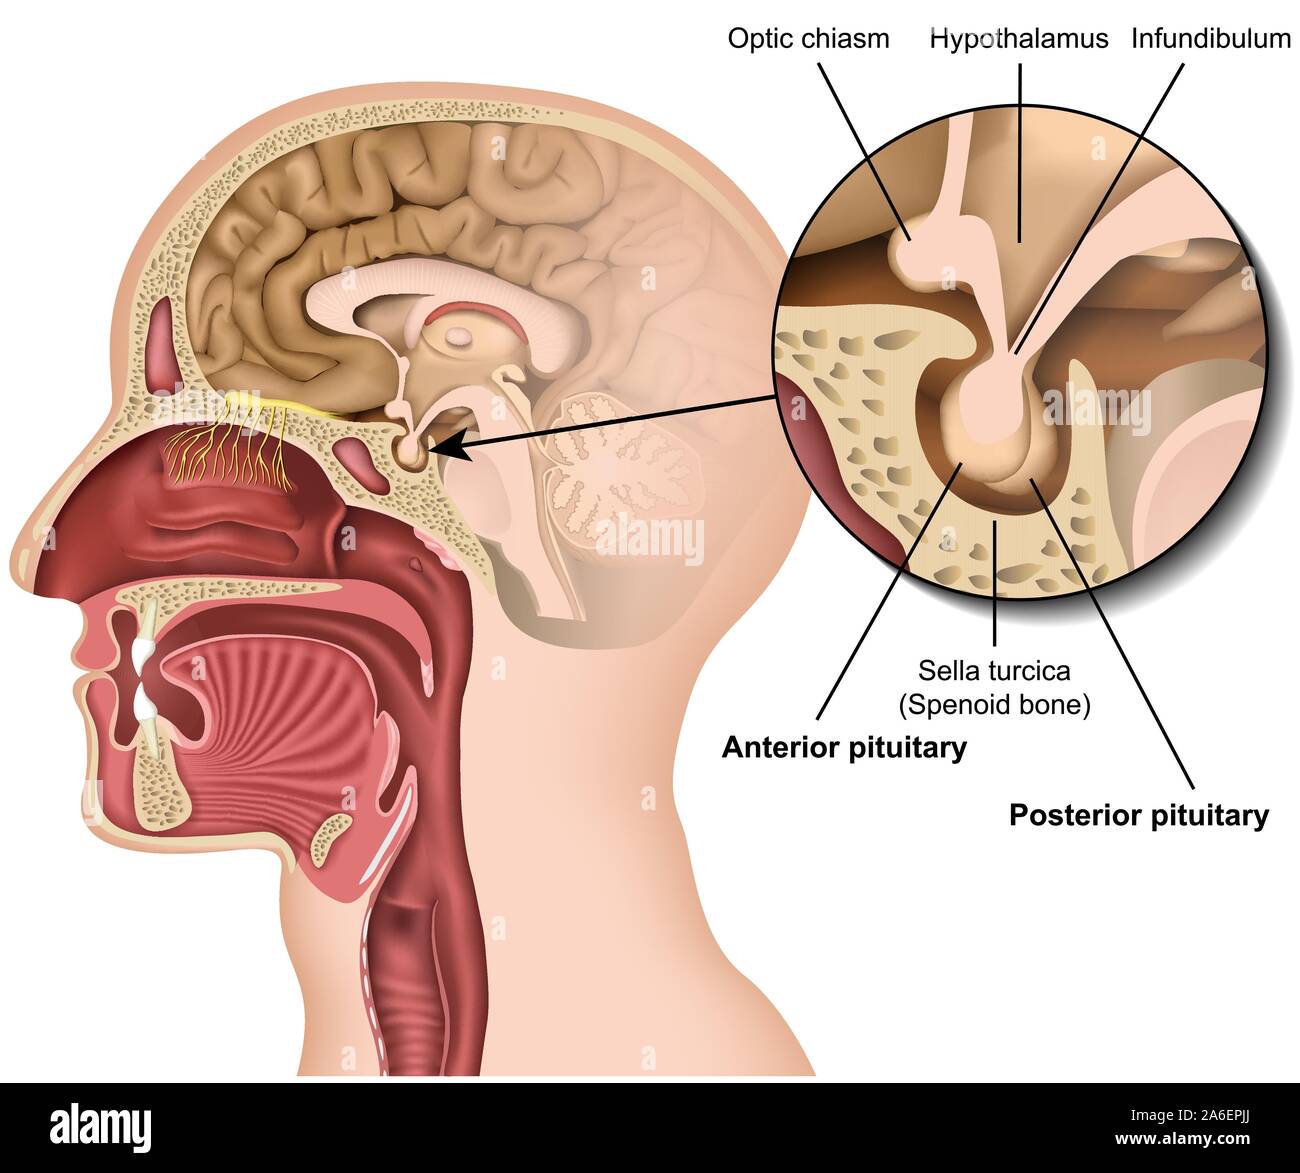

RF2PPWR9E–Cervello umano con parte del sistema limbico e corteccia cerebrale, nucleo suprachiasmatico, chiasmo ottico, Ipotalamo, E Pineal Gland

RF2KD1KYC–Adenoma ipofisario. Sezione trasversale del cervello umano. Primo piano di ipofisi. Ghiandola endocrina. Poster vettoriale

RF2A6EPJJ–Ipofisi anatomia 3d medical illustrazione vettoriale isolati su sfondo bianco ipotalamo nel cervello umano eps 10 Una infografica